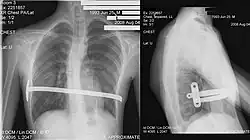

Chest x-rays are also useful in the diagnosis. The chest x-ray in pectus excavatum can show an opacity in the right lung area that can be mistaken for an infiltrate (such as that seen with pneumonia).[23] Some studies also suggest that the Haller index can be calculated based on chest x-ray as opposed to CT scanning in individuals who have no limitation in their function.[24]

Surgical correction of the pectus excavatum has been shown to significantly improve cardiovascular function;[50] there is inconclusive evidence so far as to whether it might also improve pulmonary function.[51] One of the most popular techniques for repair of pectus excavatum today is the minimally invasive operation, also known as MIRPE or Nuss technique with a system of bars made in metal.[52][53]

The minimally invasive repair of pectus excavatum known as the Nuss procedure has become a widely adopted surgical technique. This approach involves inserting a custom-bent bar into the chest to correct the sternal depression, aiming to restore a normal chest wall contour. Prior to the Nuss procedure, patients undergo thorough pre-operative evaluations, including physical examinations, imaging studies (such as CT scans to calculate the Haller index and assess cardiac compression), and cardiopulmonary function tests to determine the severity of the pectus and its impact on the heart and lungs. Studies have consistently shown positive outcomes with the Nuss procedure. For instance, an early experience with 68 patients reported that 93% achieved excellent, very good, or good results following the surgery. This procedure is also characterized by relatively short operative times (averaging around 70 minutes) and a brief hospital stay (mean of 5.7 days). While minor early complications like residual pneumothorax can occur, these often resolve spontaneously.[53]

His two-stage procedure, widely known as the Nuss procedure, involves slipping in one or more concave steel bars into the chest, underneath the sternum.[63]

The bar is flipped to a convex position so as to push outward on the sternum, correcting the deformity. The bar usually stays in the body for about two years.[53][64] When the bones have solidified into place, the bar is removed through outpatient surgery.